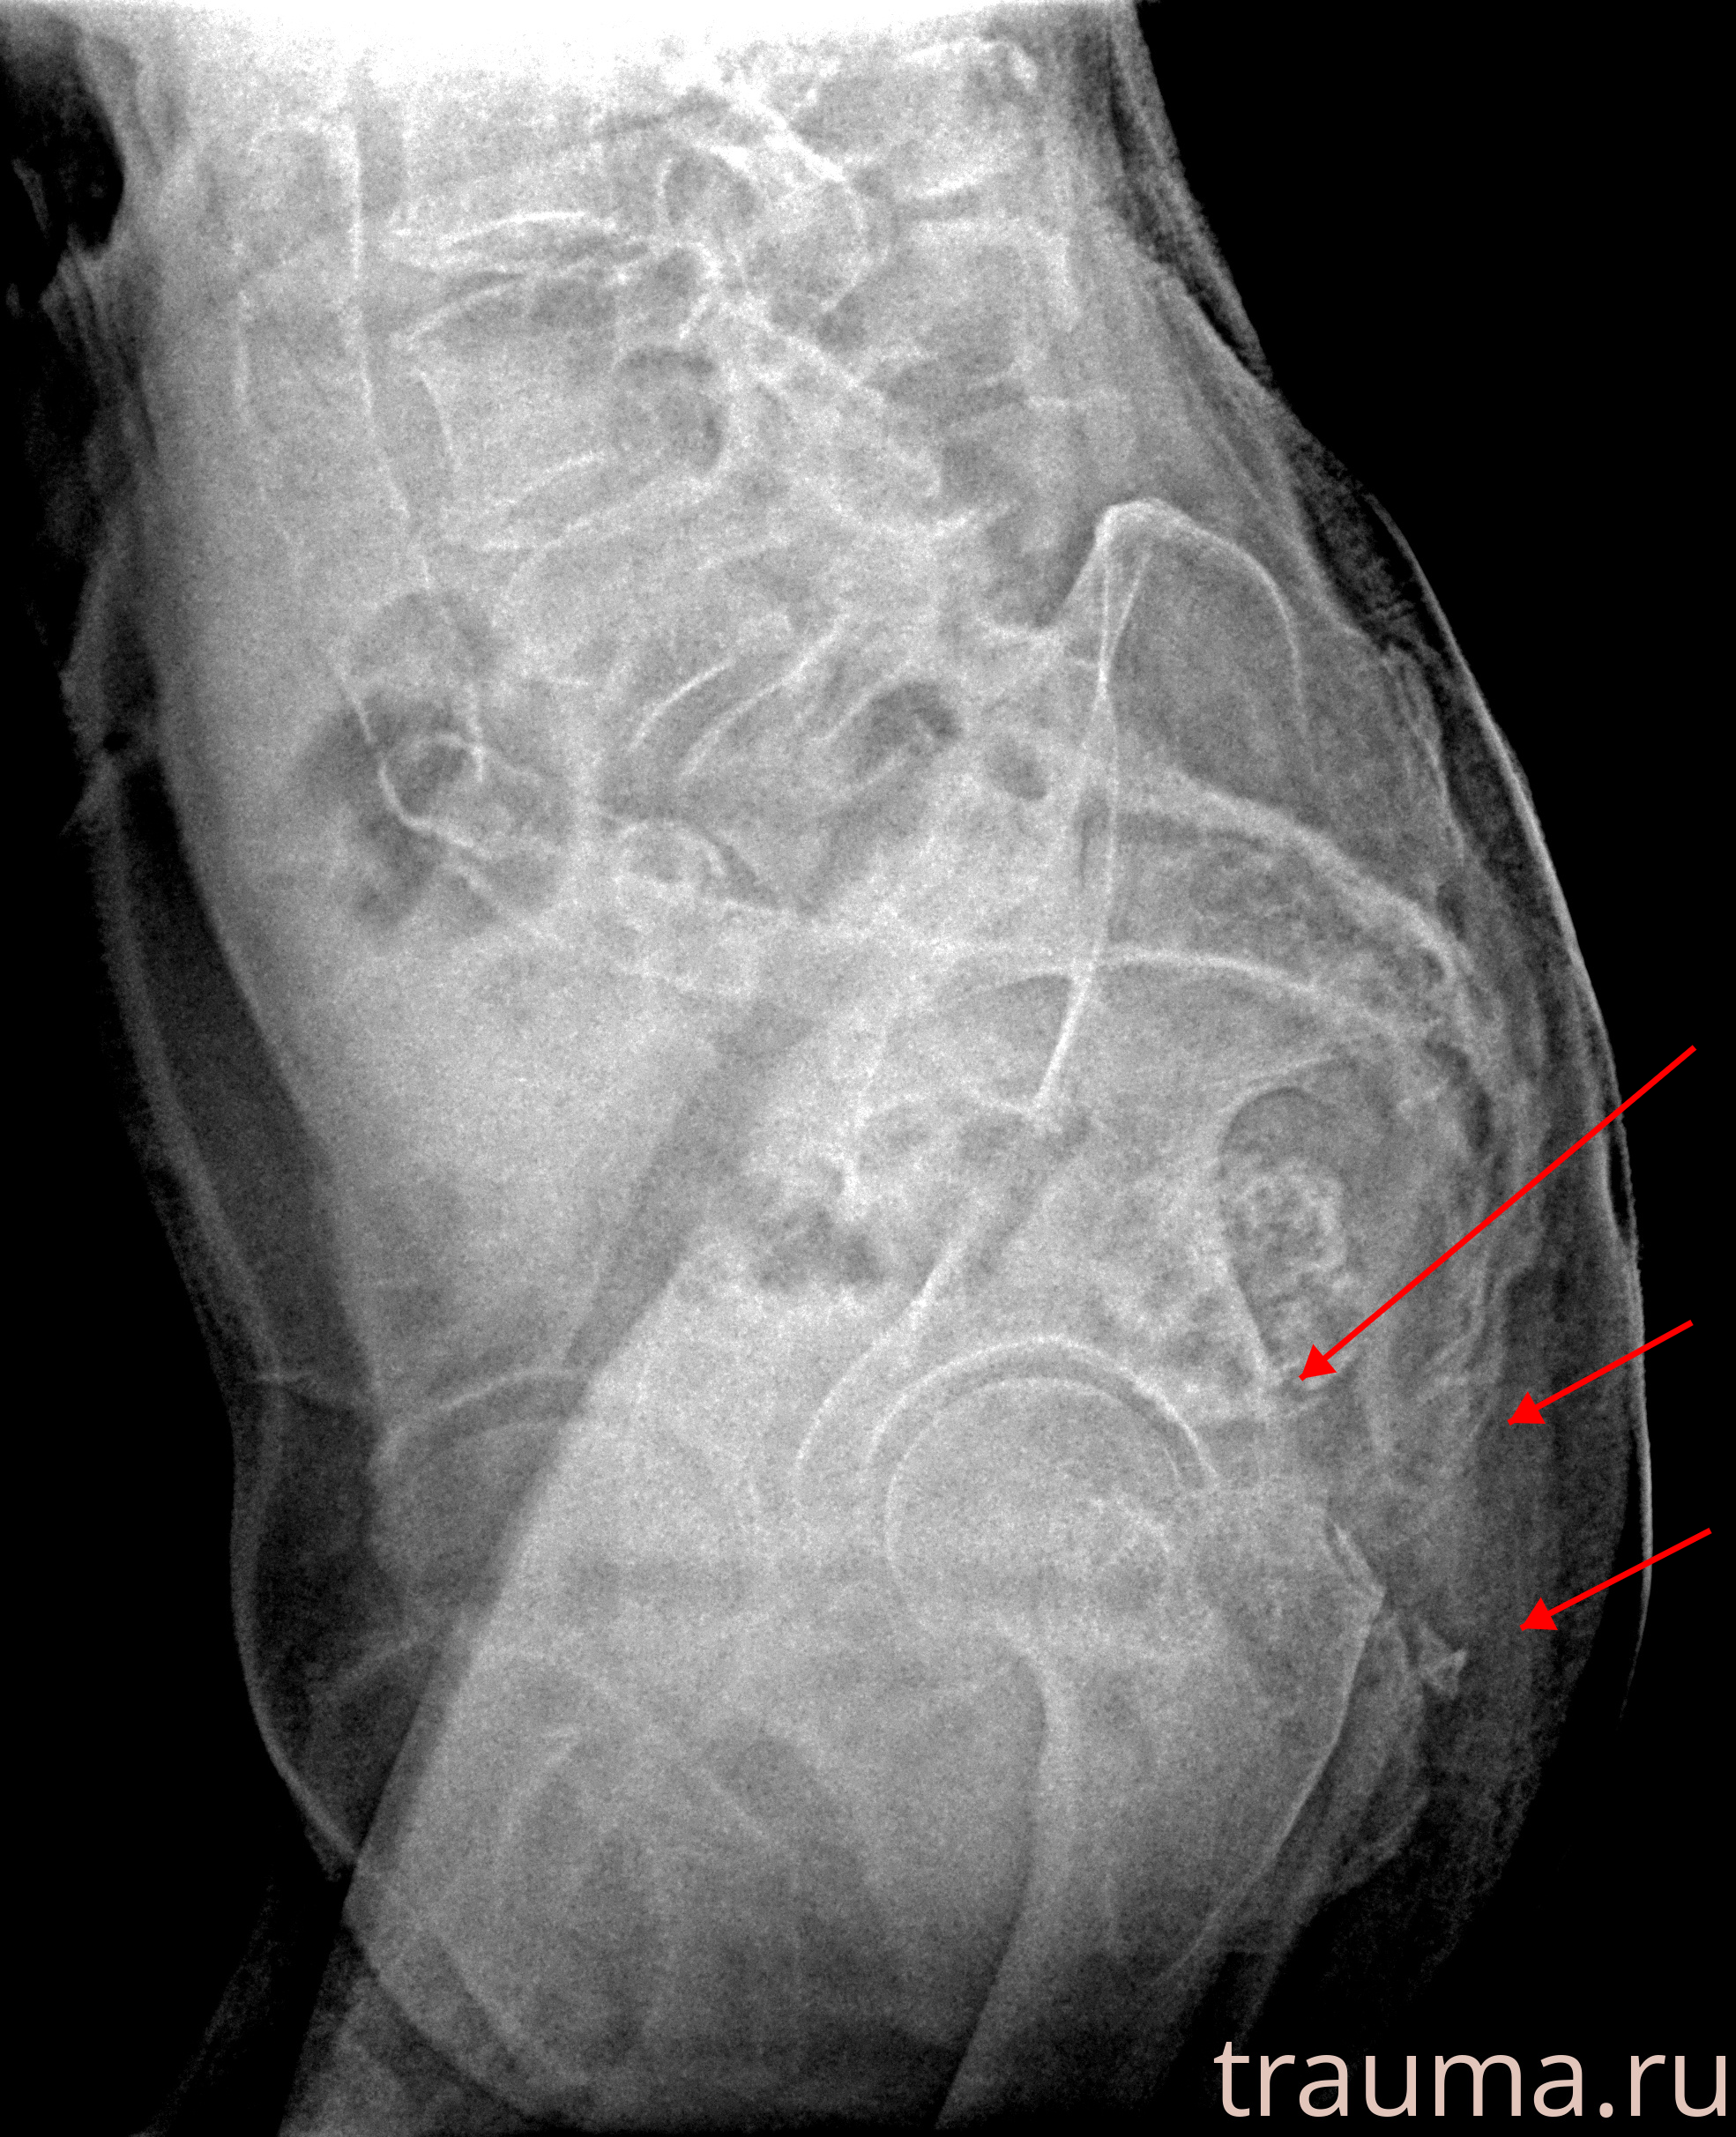

Рентгенограммы

Рентген на дому: по вашему адресу приезжает врач-рентгенолог, травматолог-ортопед с мобильным рентгеновским аппаратом, проводит диагностику травмы или заболевания, делает необходимые рентгенограммы, дает рекомендации по дальнейшему лечению. Получить качественные снимки в домашних условиях возможно благодаря уникальной методике, разработанной МосРентген Центром для института  Склифосовского